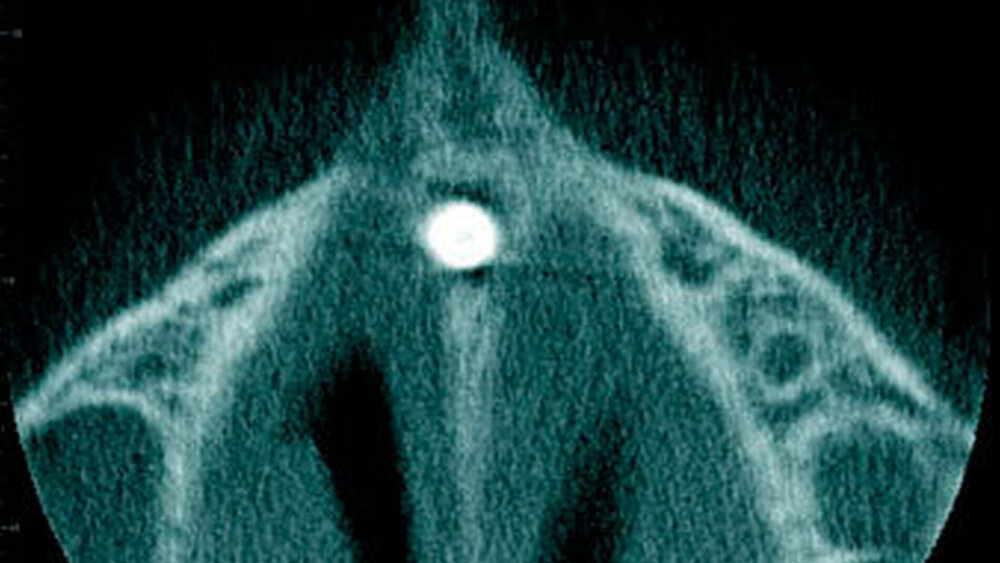

Radiologisch erscheint der Zahnfollikel um retinierte überzählige Zähne als eine dünne perikoronale Radio-luzenz, welche in der Regel nicht breiter als 3 mm ist [Mossaz et al., 2014] (Abbildung 19). Andere Autoren betrachten eine Breite von 2 mm als physiologisch [Tyrilogou et al., 2005]. Bis heute fehlen aber klare Angaben zu den normalen Dimensionen des Zahnfollikels, das heißt, es ist radiologisch nicht eindeutig zu erkennen, wann ein zystischer Prozess vorliegt [Villalba et al., 2012]. Studien berichteten über eine (pathologische) Erweiterung des Follikularraums in 1,4 Prozent bis 5,3 Prozent der überzähligen Zähne [von Arx 1990; Tyrologou et al., 2005; Liu et al., 2007; Hyun et al., 2009; Mossaz et al., 2014]. Dagegen sahen Koch und Mitarbeiter (1986) bei 54 überzähligen Zähnen keine Erweiterung des perikoronaren Raumes während des Beobachtungsintervalls (Mittelwert: 7,3 Jahre).